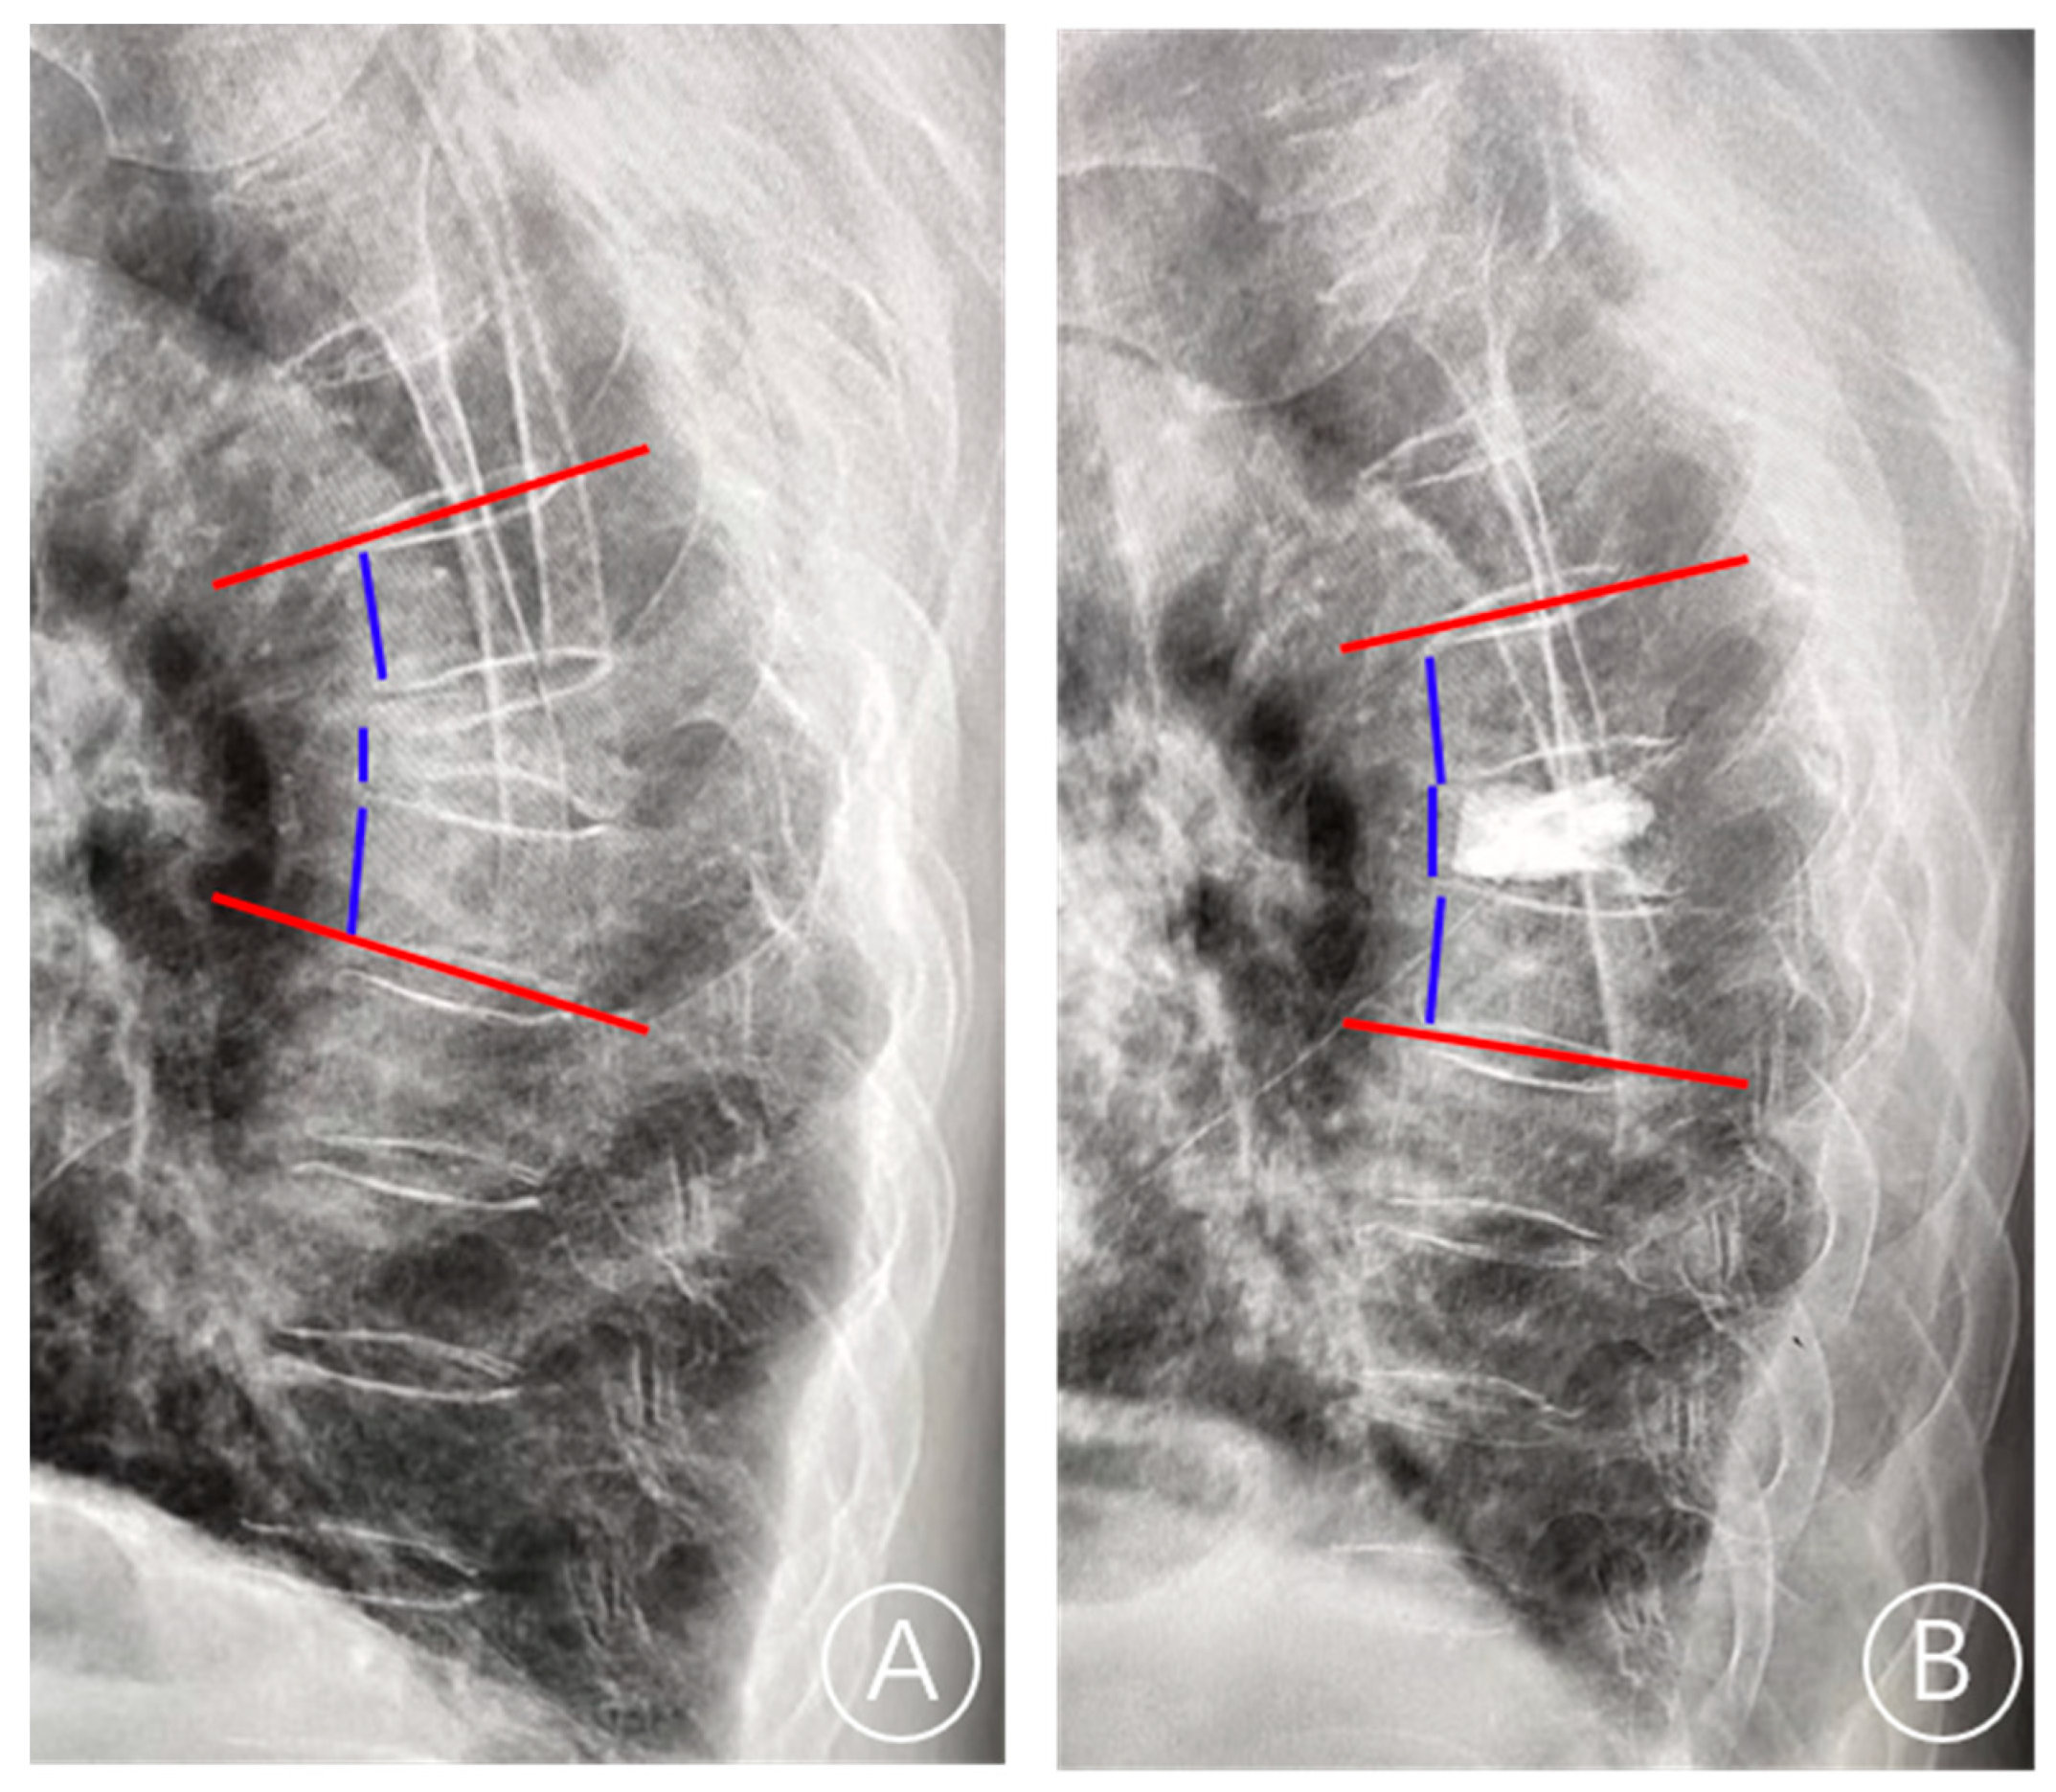

2.2. Bone Cement Displacement Diagnostic Criteria

2.4. Evaluation Index

2.5. Index Definition